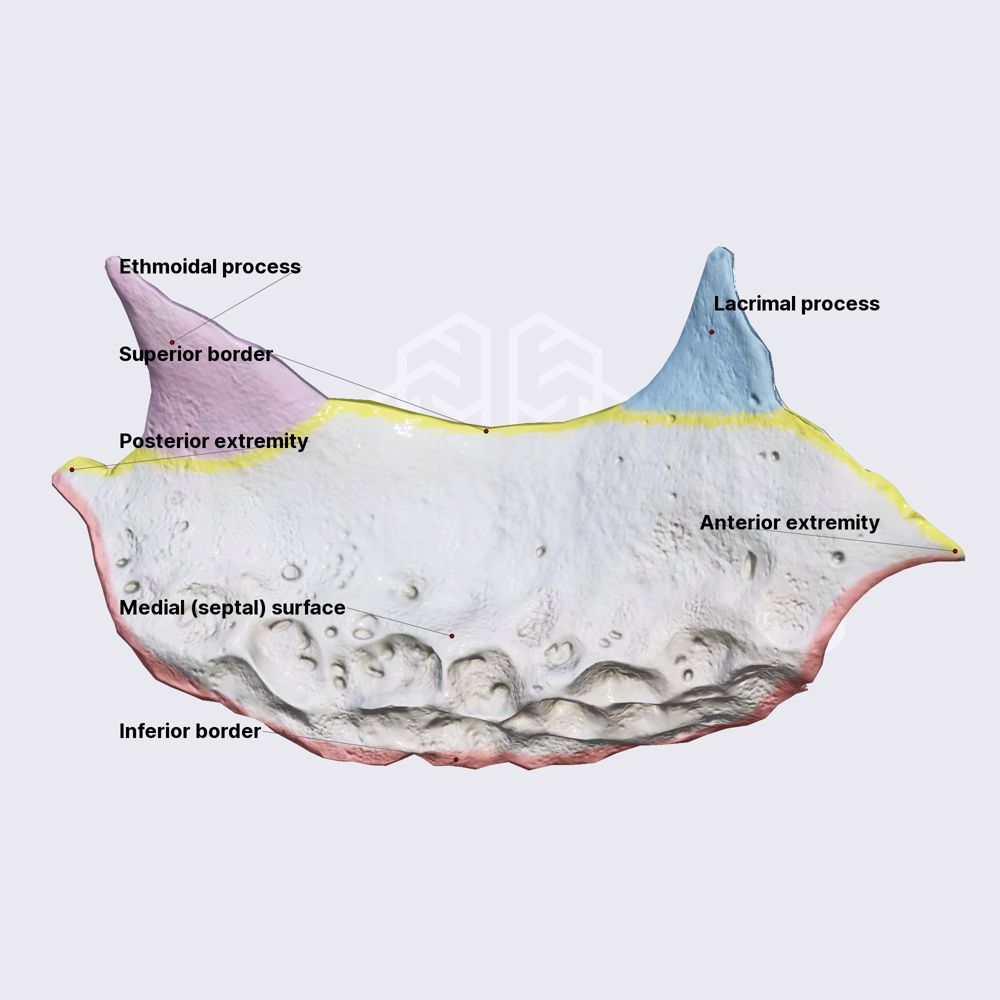

Lacrimal bone

淚囊(lacrimal sac)

相鄰 lacrimal bone, maxillary bone

相鄰骨

F, Mx, E, INC